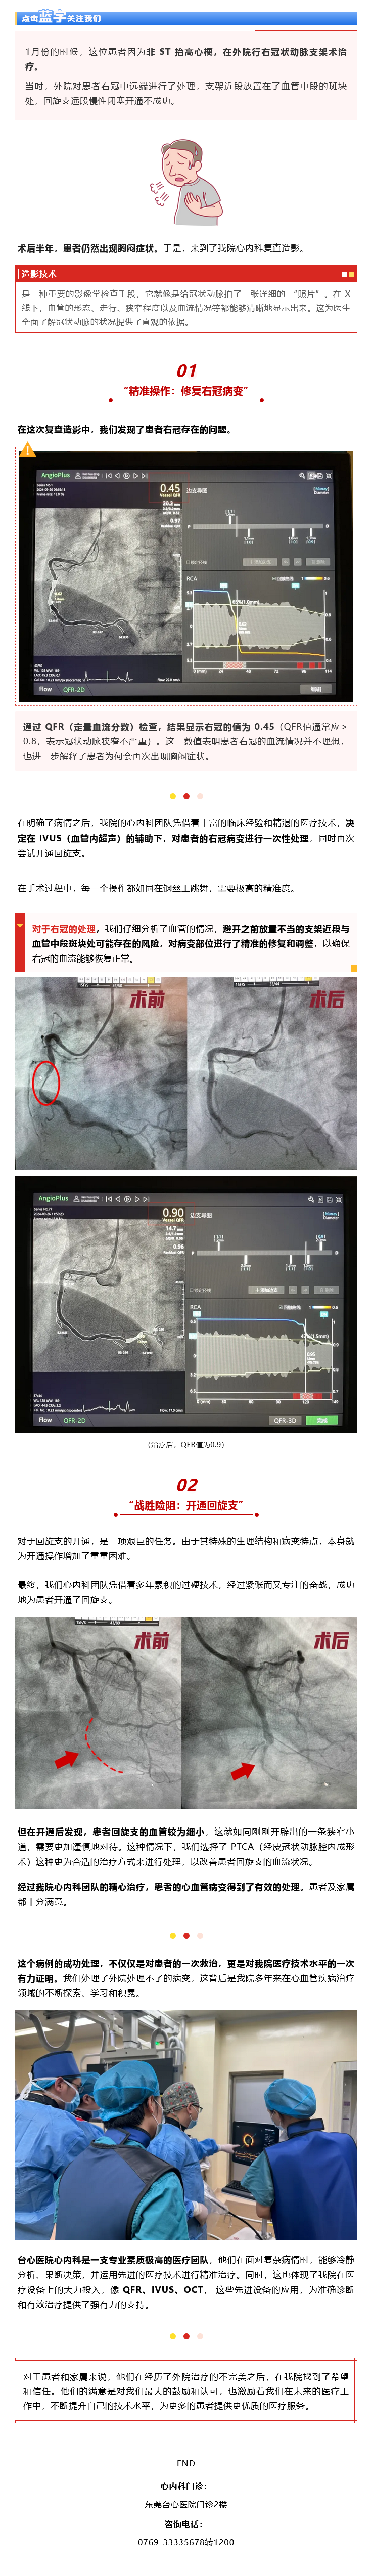

厉害!我院心内科团队成功解决外院遗留心血管病变难题